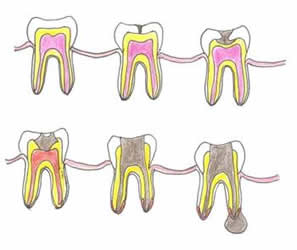

Fig 36. Diagrama de enfermedad endodontal.

Inicialmente se produce una caries, que progresa y compromete la cámara pulpar.

Posteriormente la infección se extiende por el foramen apical, hasta los tejidos periapicales y el hueso.